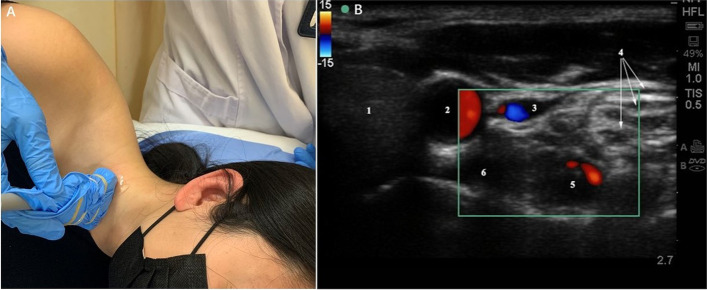

The patient’s position was similar to that of the traditional blind method. Patients were positioned in a lateral position with their necks slightly hyperextended. Assisted by ultrasound imaging equipment and a 7–14 MHz linear array probe (S-Nerve, SonoSite, USA), the C7 level was confirmed. Because of the tiny or absent anterior tubercle of the C7, sonoanatomy of the C7 transverse process was similar to the traditional Chinese “imperial concubine chair”. The thyroid gland, carotid artery, compressible internal jugular vein, vertebral artery, brachial plexus and the oval-shaped structure of the longus colli muscle were revealed on this short-axis view. The color Doppler mode was used before needling to avoid penetrating blood vessels such as the vertebral artery, internal jugular vein and inferior thyroid vessel (Fig. 1).

Fig. 1.

Ultrasonic exploration of stellate ganglion. A: Patient’s position and placement of ultrasound probe. B: Ultrasound image of the cervical structure during stellate ganglion block.1, thyroid; 2, common carotid artery; 3, internal jugular vein; 4, brachial plexus; 5, vertebral artery; 6, longus colli muscle